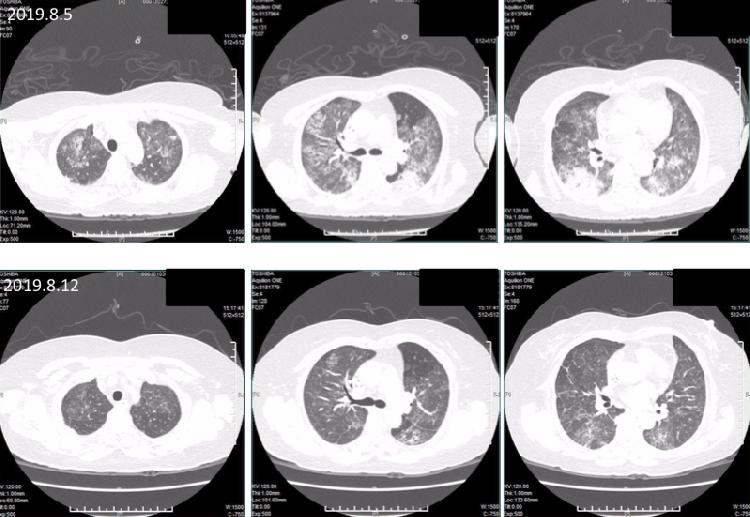

(非案例患者检查报告,仅用于说明治疗后效果)

一次血浆置换治疗需进行2~3个小时,期间有一名护士寸步不离地守在陈阿姨病床旁,时刻关注着她的生命体征,保障其安全。10天后,陈阿姨经过5次血浆置换治疗,各种不适症状逐步减轻,生命体征平稳,CT检查结果显示她的心包积液、胸腔积液完全吸收。这也意味着,血浆置换+糖皮质激素+免疫抑制剂+控制感染治疗成功帮助陈阿姨“换”出了新生,她能够挥别免疫系统突然“失控”的噩梦,通过保持规律随访治疗,重新开始正常的工作和生活。